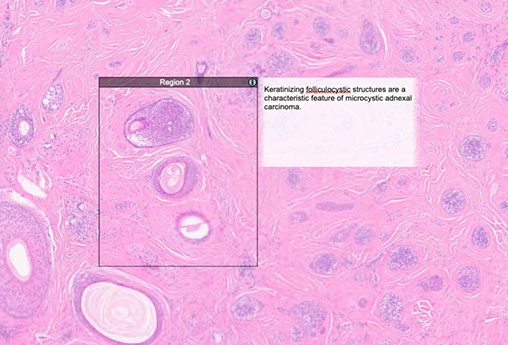

Microcystic adnexal carcinoma (MAC)

Biphasic c hairs and sweat ducts, also with the infiltrative tadpole glands, sclerotic stroma that can extend all the way to sk muscle

- poorly circumscribed

- perineural invasion common

- rarely have calcifications

- lymph aggs are common

- there is not much atypia

- look for perineural invasion to dx MAC (will not see in discoid trichoepithelioma)

The basic histologic pattern of MAC: variably sized ducts, nests, and cords of basaloid cells with clear-to-eosinophilic cytoplasm. The cellular differentiation of the outer root sheath of the hair follicular (trichilemmal) and many of the nests appear to recapitulate the structure of a primitive hair follicle

At least focal ductal differentiation required to dx MAC